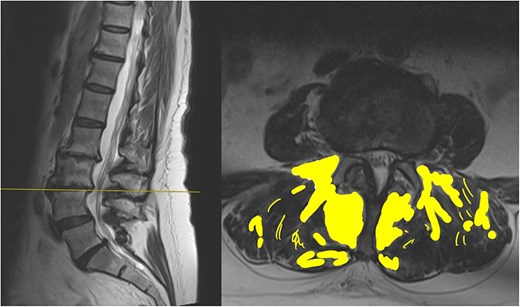

The MRI report detailed the vertebral bodies, discs, and spinal cord but did not comment on the surrounding spinal musculature. On review of the images, no clear impingement of the spinal nerves was seen (Fig. 2). It was, however, noted that there was significant fat infiltration of the paraspinal muscles (Fig. 3).

Sagittal and axial section at L3/4. The fat infiltration is highlighted in a yellow shade in this image.